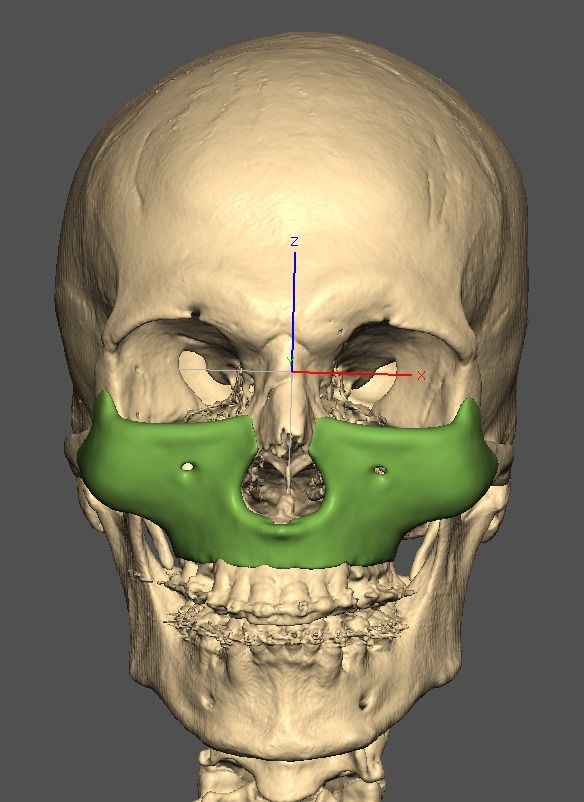

I know a guy who designed this for himself in collaboration with an asian implant company.

Not the final product yet, he is making adjustments as we speak.

Giant and Eppley were the inspiration